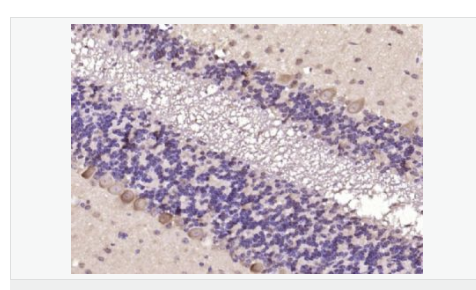

產(chǎn)品介紹Representing about 2% of human DNA, chromosome 20 consists of approximately 63 million bases and 600 genes. Chromosome 20 contains a region with numerous genes expressed in the epididymis, which are thought important for seminal production, and some viewed as potential targets for male contraception. The PRNP gene encoding the prion protein associated with spongiform encephalopathies, like Creutzfeldt-Jakob disease, is found on chromosome 20. Amyotrophic lateral sclerosis, spinal muscular atrophy, ring chromosome 20 epilepsy syndrome and Alagille syndrome are also associated with chromosome 20. The C20orf160 gene product has been provisionally designated C20orf160 pending further characterization.

Similarity:

Belongs to the CCM2 family.